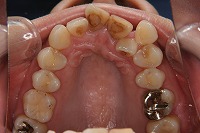

上顎

前歯が出ていて歯並びが悪い事を主訴に来院された、26歳1か月の女性です。診断「歯と歯槽基底の大きさの不調和による叢生」上顎は右側第1小臼歯と左側の犬歯、下顎は抜歯をせず治療を行いました。